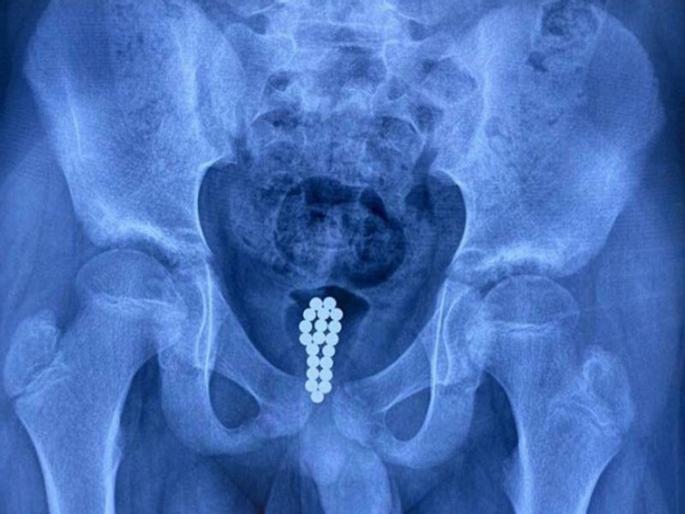

डॉक्टरांनी एका व्यक्तीच्या प्रायव्हेट पार्टमधून लोह चुंबकाची चेन काढली. यात २९ मॅग्नेटिक बॉल्स होते. डॉक्टरांनी फार मेहनतीनंतर या व्यक्तीच्या शरीरातून ही चेन बाहेर काढली.

ही घटना चीनच्या शांक्सीमधून समोर आली आहे. इथे राहणाऱ्या एका व्यक्तीला सीटी स्कॅननंतर लगेट हॉस्पिटलमध्ये भरती करण्यात आलं. कारण डॉक्टरांना सीटी स्कॅनमध्ये काही मॅग्नेटिक बॉल्स दिसले.

शांक्सीतील पीपल्स हॉस्पिटलमध्ये काम करणारे यूरोलॉजिस्ट क्यू ली मिंग यांनी एका न्यूज चॅनेलला दिलेल्या मुलाखतीत सांगितले की, या व्यक्तीच्या ब्लॅडरमध्ये अनेक मॅग्नेटिक बॉल्स होते.

हे बॉल्स सर्जरी करून बाहेर काढण्यात आलेत. डॉक्टरांना ब्लॅडरमधून हे मॅग्नेटिक बॉल्स बाहेर काढण्यासाठी बराच वेळ लागला.

हे मॅग्नेटिक बॉल्स आत टाकल्यावर १० दिवसांनी व्यक्तीच्या प्रायव्हेट पार्टमधून रक्त येत होतं. त्यानंतर तो लगेच हॉस्पिटलमध्ये गेला. तेव्हा डॉक्टरांना सीटी स्कॅनमध्ये हे बॉल्स दिसले.